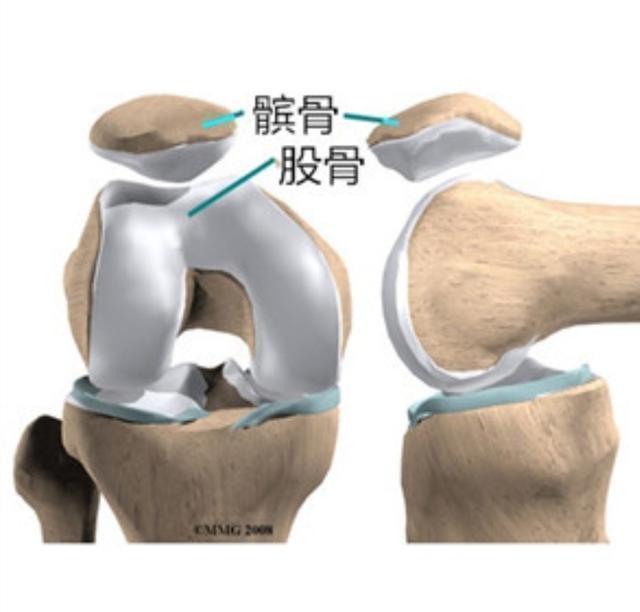

我们的膝关节实际上有三块骨头组成,分别是大腿骨,小腿骨,还有膝盖正面的、圆形的髌骨。髌骨是我们每个人都能摸到的,你用手放在你的膝盖正前方就能触摸到一个圆形的,像盖子一样的圆骨头,只要你的大腿肌肉是放松状态,那么髌骨就是可以左右推动的。那么既然是三块骨头,它们就构成了两个不同的接触面。一个呢,很好理解,是大腿和小腿骨之间的接触面,这个关节面是让我们负重用的。不论我们是站着、走路、跳跃,只要有体重压在膝盖上,这个关节面就承担压力。而我们人体膝关节的结构,决定了内侧关节受力多,约占整个重量的60?外侧关节面受力少,约占40?所以往往都是膝盖内侧磨损的快,内侧关节间隙,首先出现狭窄,所以很多人膝关节炎,刚开始的症状会有膝盖内侧的疼痛,久而久之,也会出现O型腿,也叫膝内翻,这就是因为膝盖内侧的软骨等结构已经被磨损殆尽。

如图所示,内侧关节缝隙比外侧变得狭窄了,膝盖的外观也就变成罗圈腿了。当出现这些症状的时候,我们就会开始出现走路疼痛。一般都是先有内侧疼,然后逐渐发展到整个关节都疼。等到走平地都不能走了,每一步都疼的时候,往往这个时候就需要做保膝手术或关节置换等手术治疗了。除此之外呢,我们的膝盖还有一个关节面,叫做髌股关节。也就是刚才我们摸的那个圆骨头深部的软骨面。这个部位比较特殊,当我们伸直腿,也就是走路的时候,这个关节面的压力是比较小的,甚至软骨和软骨之间都是不接触的。这是为什么刚才我们在伸直并放松大腿肌肉的时候,髌骨可以推动的原因。

但是当我们膝盖弯曲的时候,我们发现髌骨无法推动了,这是因为当弯曲膝盖的时候,髌骨被压在了股骨上,两个关节面的软骨开始受压,摩擦。所以说,当我们在上下楼梯,蹲起,坐着起来,爬山爬坡等等,需要弯曲膝盖使劲的动作的时候,髌股关节面会承担负荷,久而久之会产生磨损。当我们的大腿和小腿之间的关节面保存的还可以,而髌股关节之间的关节面磨损的比较严重的时候,我们就会开始出现上下楼梯疼,爬山爬坡疼,蹲下起来疼,但是走平地不疼的现象。【 咋回事|膝关节很奇怪,上下楼梯,蹲起蹲起就疼,走平路不疼,咋回事】